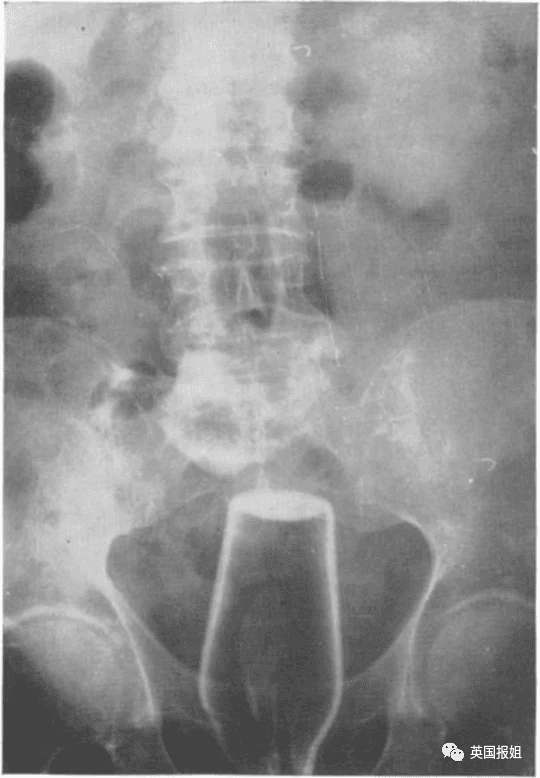

图中的患者是一名72岁的老翁,他自称在上厕所时不慎跌倒在了一个倒着的酒瓶上:

去年印度某医院急诊部闯入一名醉汉,该男子手拎着一根水管子,水管的另一头通向他的屁股。

拍完X光后,当天的值班医生和工作人员都惊呆了,男子竟然将一整个水龙头塞进了后面...

可以想象他走进医院的时候,就像一个长了尾巴的人。由于患者把水龙头塞得太深,他的直肠被穿透,经过了一场大手术后还躺在重症监护室中。

据他的同事说,该男子醉酒后“在浴室里摔倒,坐在了水龙头上”。医生表示:“我们将采纳病人的说法,并进行下一步调查。”